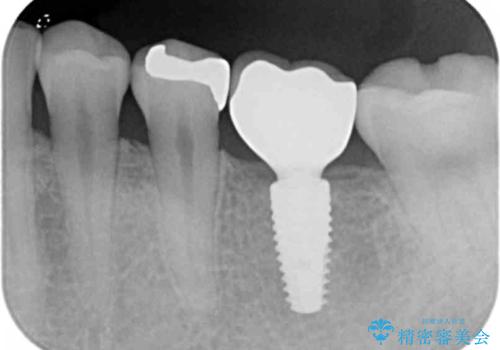

全顎的 虫歯治療 インプラント補綴

- 「他院で虫歯治療を行っているが、延々終わらず数年経過している。全体的な治療を希望したい。」と全顎的な治療を希望され来院されました。

・再発した虫歯

・銀歯の下にできた虫歯

・根尖性歯周炎

・残根状態の歯

など、虫歯を原因とする問題が多発した状態です。

今後延々と治療を繰り返さないために、全ての銀歯を外し虫歯を丁寧に取り切り、根管治療を行い、残せない歯は抜去を行った上でインプラント治療を行っていくことで全体的な治療を計画していくこととなりました。